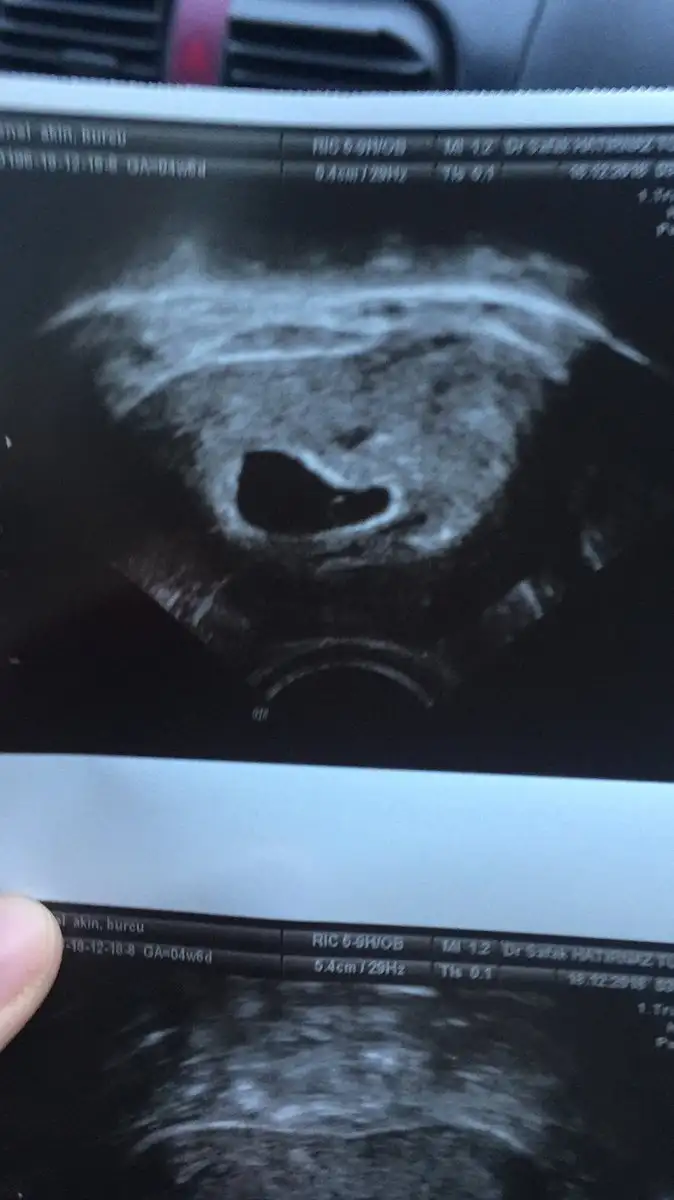

EMinim valla canim son adet tarihim 14 kasim aonra yumurta takibi ve catlarma ignesi oldum hamile kaldim anlamadimErgen karından 24 mm se çok büyük degilmi yani sen 4+6 oldugunu eminmisin yolk sac bile 6 haftalıkken gözüküyor